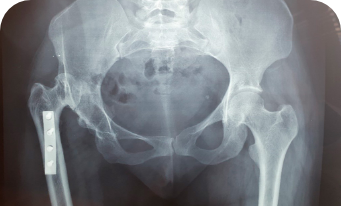

Na Ortopedia Pediátrica, o uso de técnicas modernas e abordagem personalizada são fundamentais para garantir um cuidado de excelência. Cada tratamento é cuidadosamente planejado, considerando as necessidades específicas de cada criança, desde o manejo de fraturas até correções complexas de deformidades congênitas e patologias do quadril infantil.

Displasia do desenvolvimento do quadril (DDQ)

Subluxação e Luxação do Quadril

Osteotomia do quadril